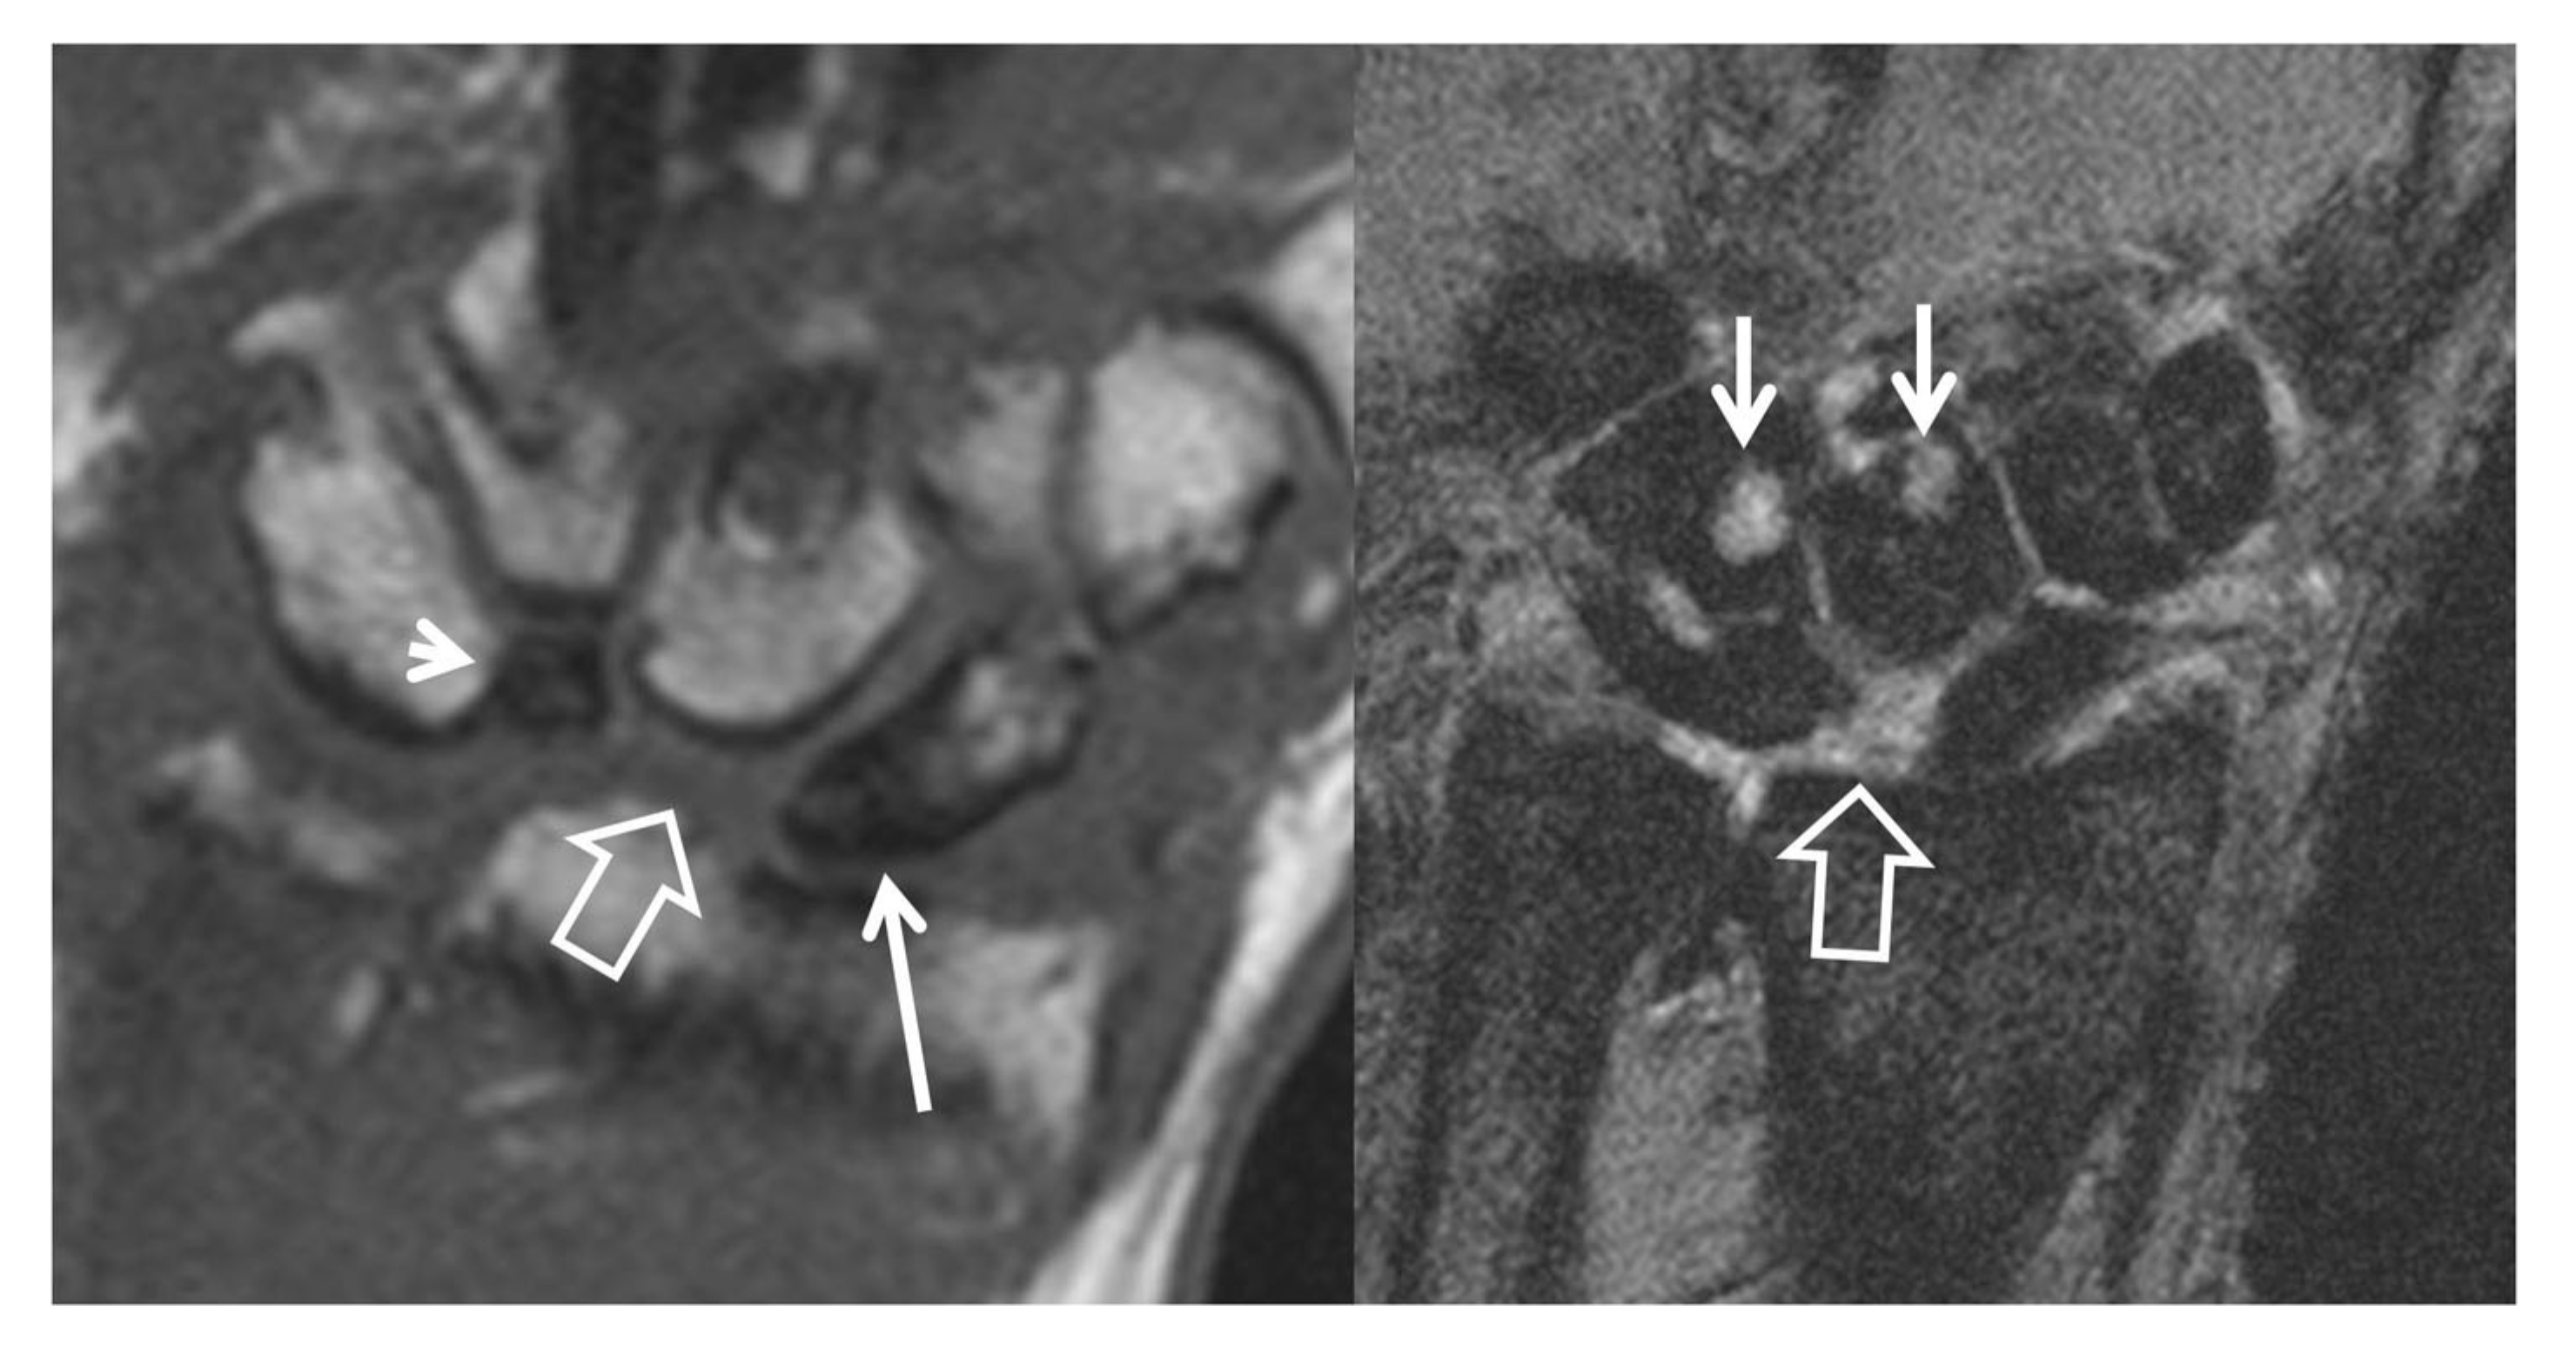

Figure 11.

Two patients with scaphoid fracture non-union, fat suppressed contrast enhanced T1w coronal MR images. Both images show the fracture line (thin arrows) and the normal enhancement following a fracture, of the distal pole of the scaphoid bones (thick arrows). (A) Enhancement of the proximal pole suggests viable bone marrow (open arrow). (B) Absence of any enhancement of the proximal pole suggests nonviable bone marrow (open arrow). The signal intensity of the proximal pole is lower as compared to the normal bone marrow of the surrounding bones.